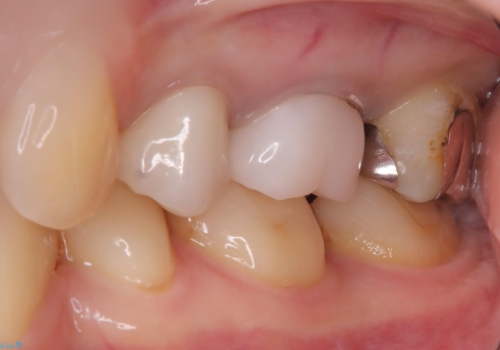

保険のメタルインレーから二次う蝕予防(保険のメタルインレーは腐食しやすかったり、適合があまり良くなかったりで二次的にう蝕がインレー下で広がってしまうことが多々あります。)のためのやり替えだったため、材料としてセラミックとゴールドを提案したところ、展延性に優れ違和感の少ないゴールドを選択されました。

・ゴールドクラウン 110,000円(税込み 121,000円)

・仮歯 10,000円(税込み 11,000円)